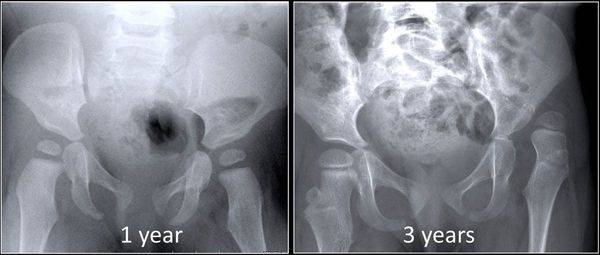

Применение описанной технологии позволяет ликвидировать спастические сокращения мускулатуры, восстановить укороченные мышцы, ликвидировать подвывихи в суставах. Постепенно, при возрастающей двигательной активности ребенка, происходит восстановление нарушенной конгруэнтности суставных поверхностей и исправление костных деформаций (фото 41-42).